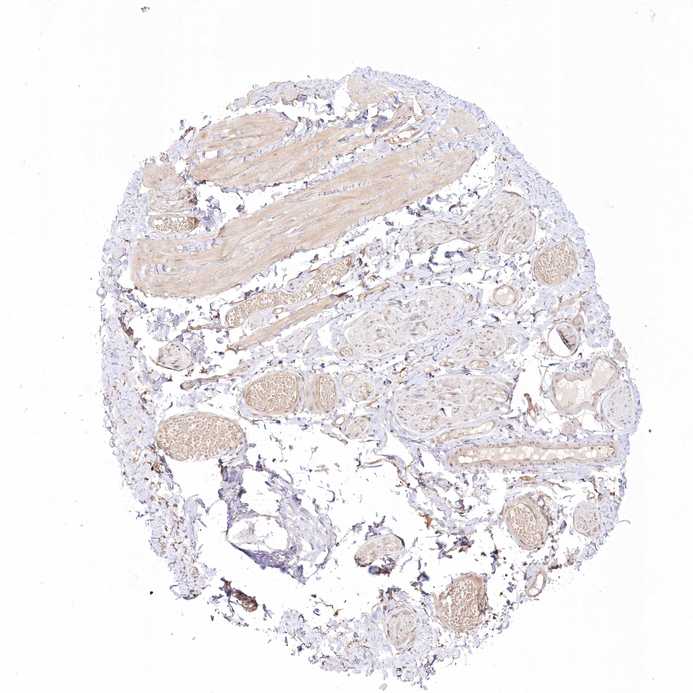

SOFT TISSUE 2 - Antibody stainingi

Antibody staining in the annotated cell types in the current human tissue is reported as not detected, low, medium, or high, based on conventional immunohistochemistry profiling in selected tissues. This score is based on the combination of the staining intensity and fraction of stained cells.

Each image is clickable and will lead to virtual microscopy that enables deeper exploration of all samples and also displays staining intensity scores, fraction scores and subcellular localization as well as patient and tissue information for each sample.

Antibody HPA037681Antibody HPA037682

Chondrocytes -Not detected

Fibroblasts MediumLow

Peripheral nerve Medium-